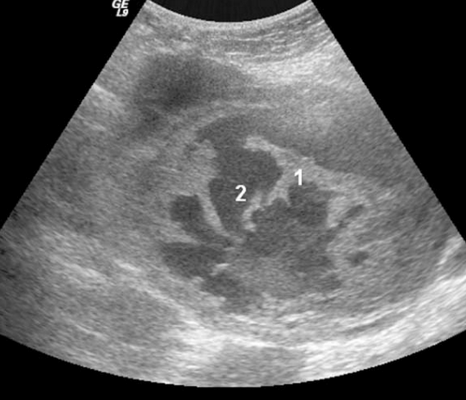

Рис.3. Метастазы опухолей верхних отделов пищеварительного тракта (желчного пузыря, желчных протоков, поджелудочной железы): многокамерная-солидная опухоль с небольшими камерами (1) и с твердым компонентом (2).

Метастазы первичного рака желчного пузыря, желчных протоков и поджелудочной железы визуализируются как многокамерные-солидные образования с многочисленными мелкими разного размера камерами без некроза. Опухоли были различной эхогенности с гиперэхогенными перегородками, с изоэхогенным или гиперэхогенным твердым компонентом. Опухоли и перегородки были гиперваскуляризованы (Рис.3).